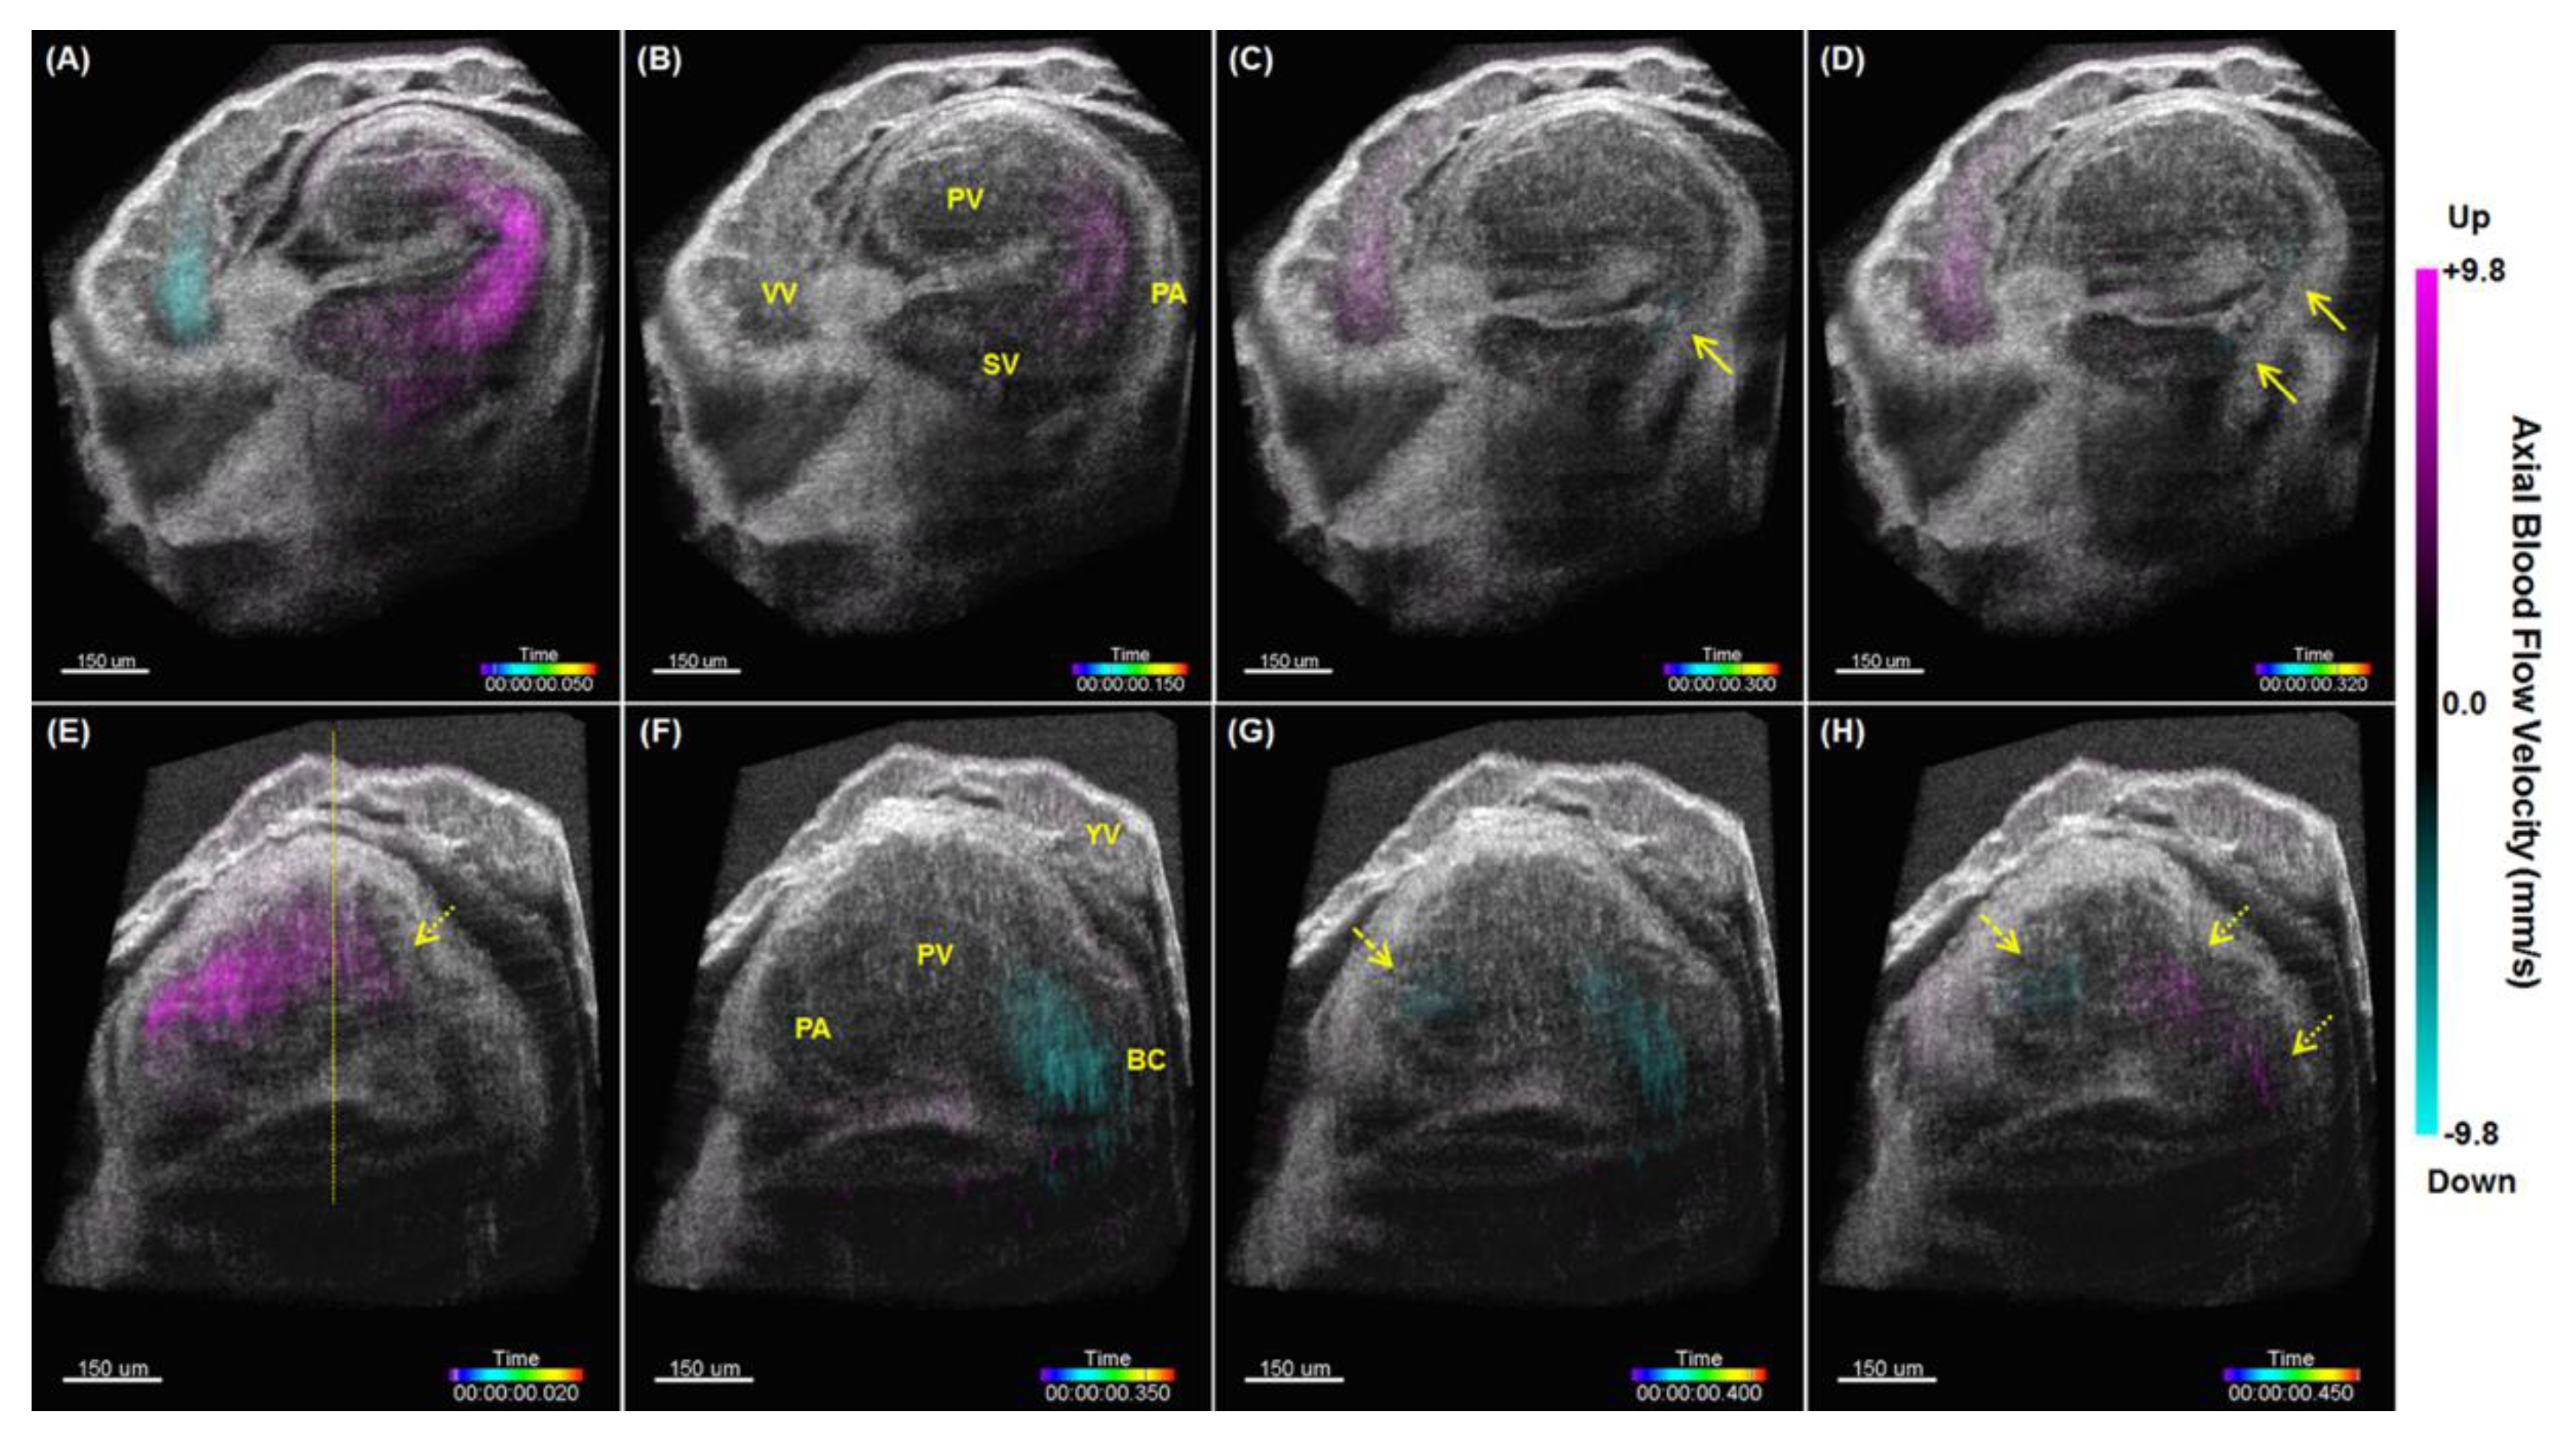

- Wang, S.; Lakomy, D.S.; Garcia, M.D.; Lopez, A.L.; Larin, K.V.; Larina, I.V. Four-dimensional live imaging of hemodynamics in mammalian embryonic heart with Doppler optical coherence tomography. J. Biophotonics 2016, 9, 837–847. [Google Scholar] [CrossRef]

- Wang, S.; Larina, I.V. Live mechanistic assessment of localized cardiac pumping in mammalian tubular embryonic heart. J. Biomed. Opt. 2020, 25, 086001. [Google Scholar] [CrossRef]